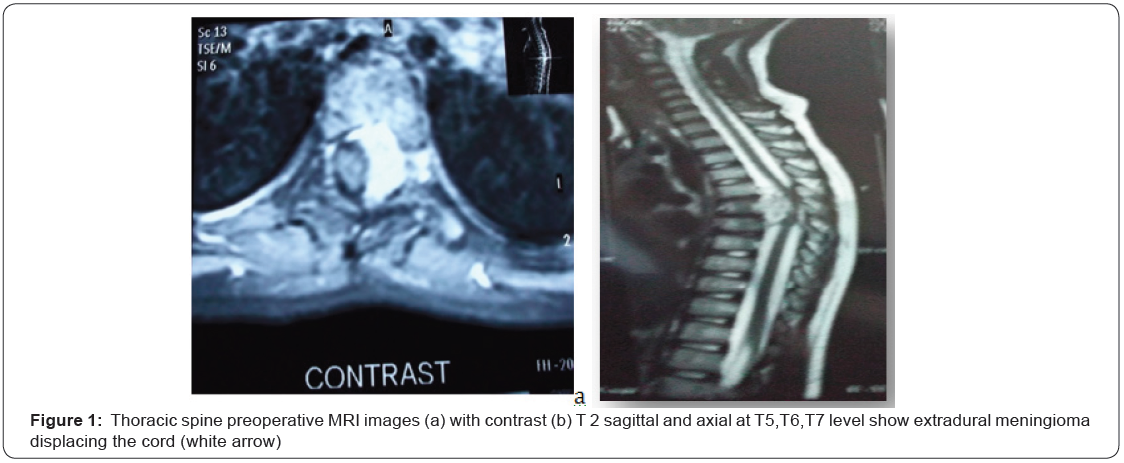

OAJNN.MS.ID.555659